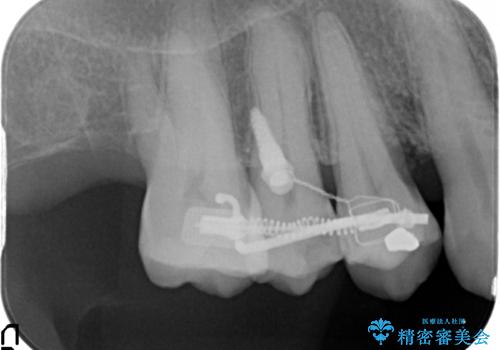

検査の結果、強い歯ぎしりによる歯の周囲の骨の吸収が認められたため歯槽骨の再生・歯周ポケットの除去・力に対抗する連結補綴・補綴前処置としての小矯正を計画します。

今回連結補綴を行うにあたり、歯周病の問題を解決するために再生療法・歯周ポケット除去手術を、またより歯の神経を保存し力に対抗できる環境を整えるために小矯正を行い精度の高いメタルボンドクラウンを製作することができました。